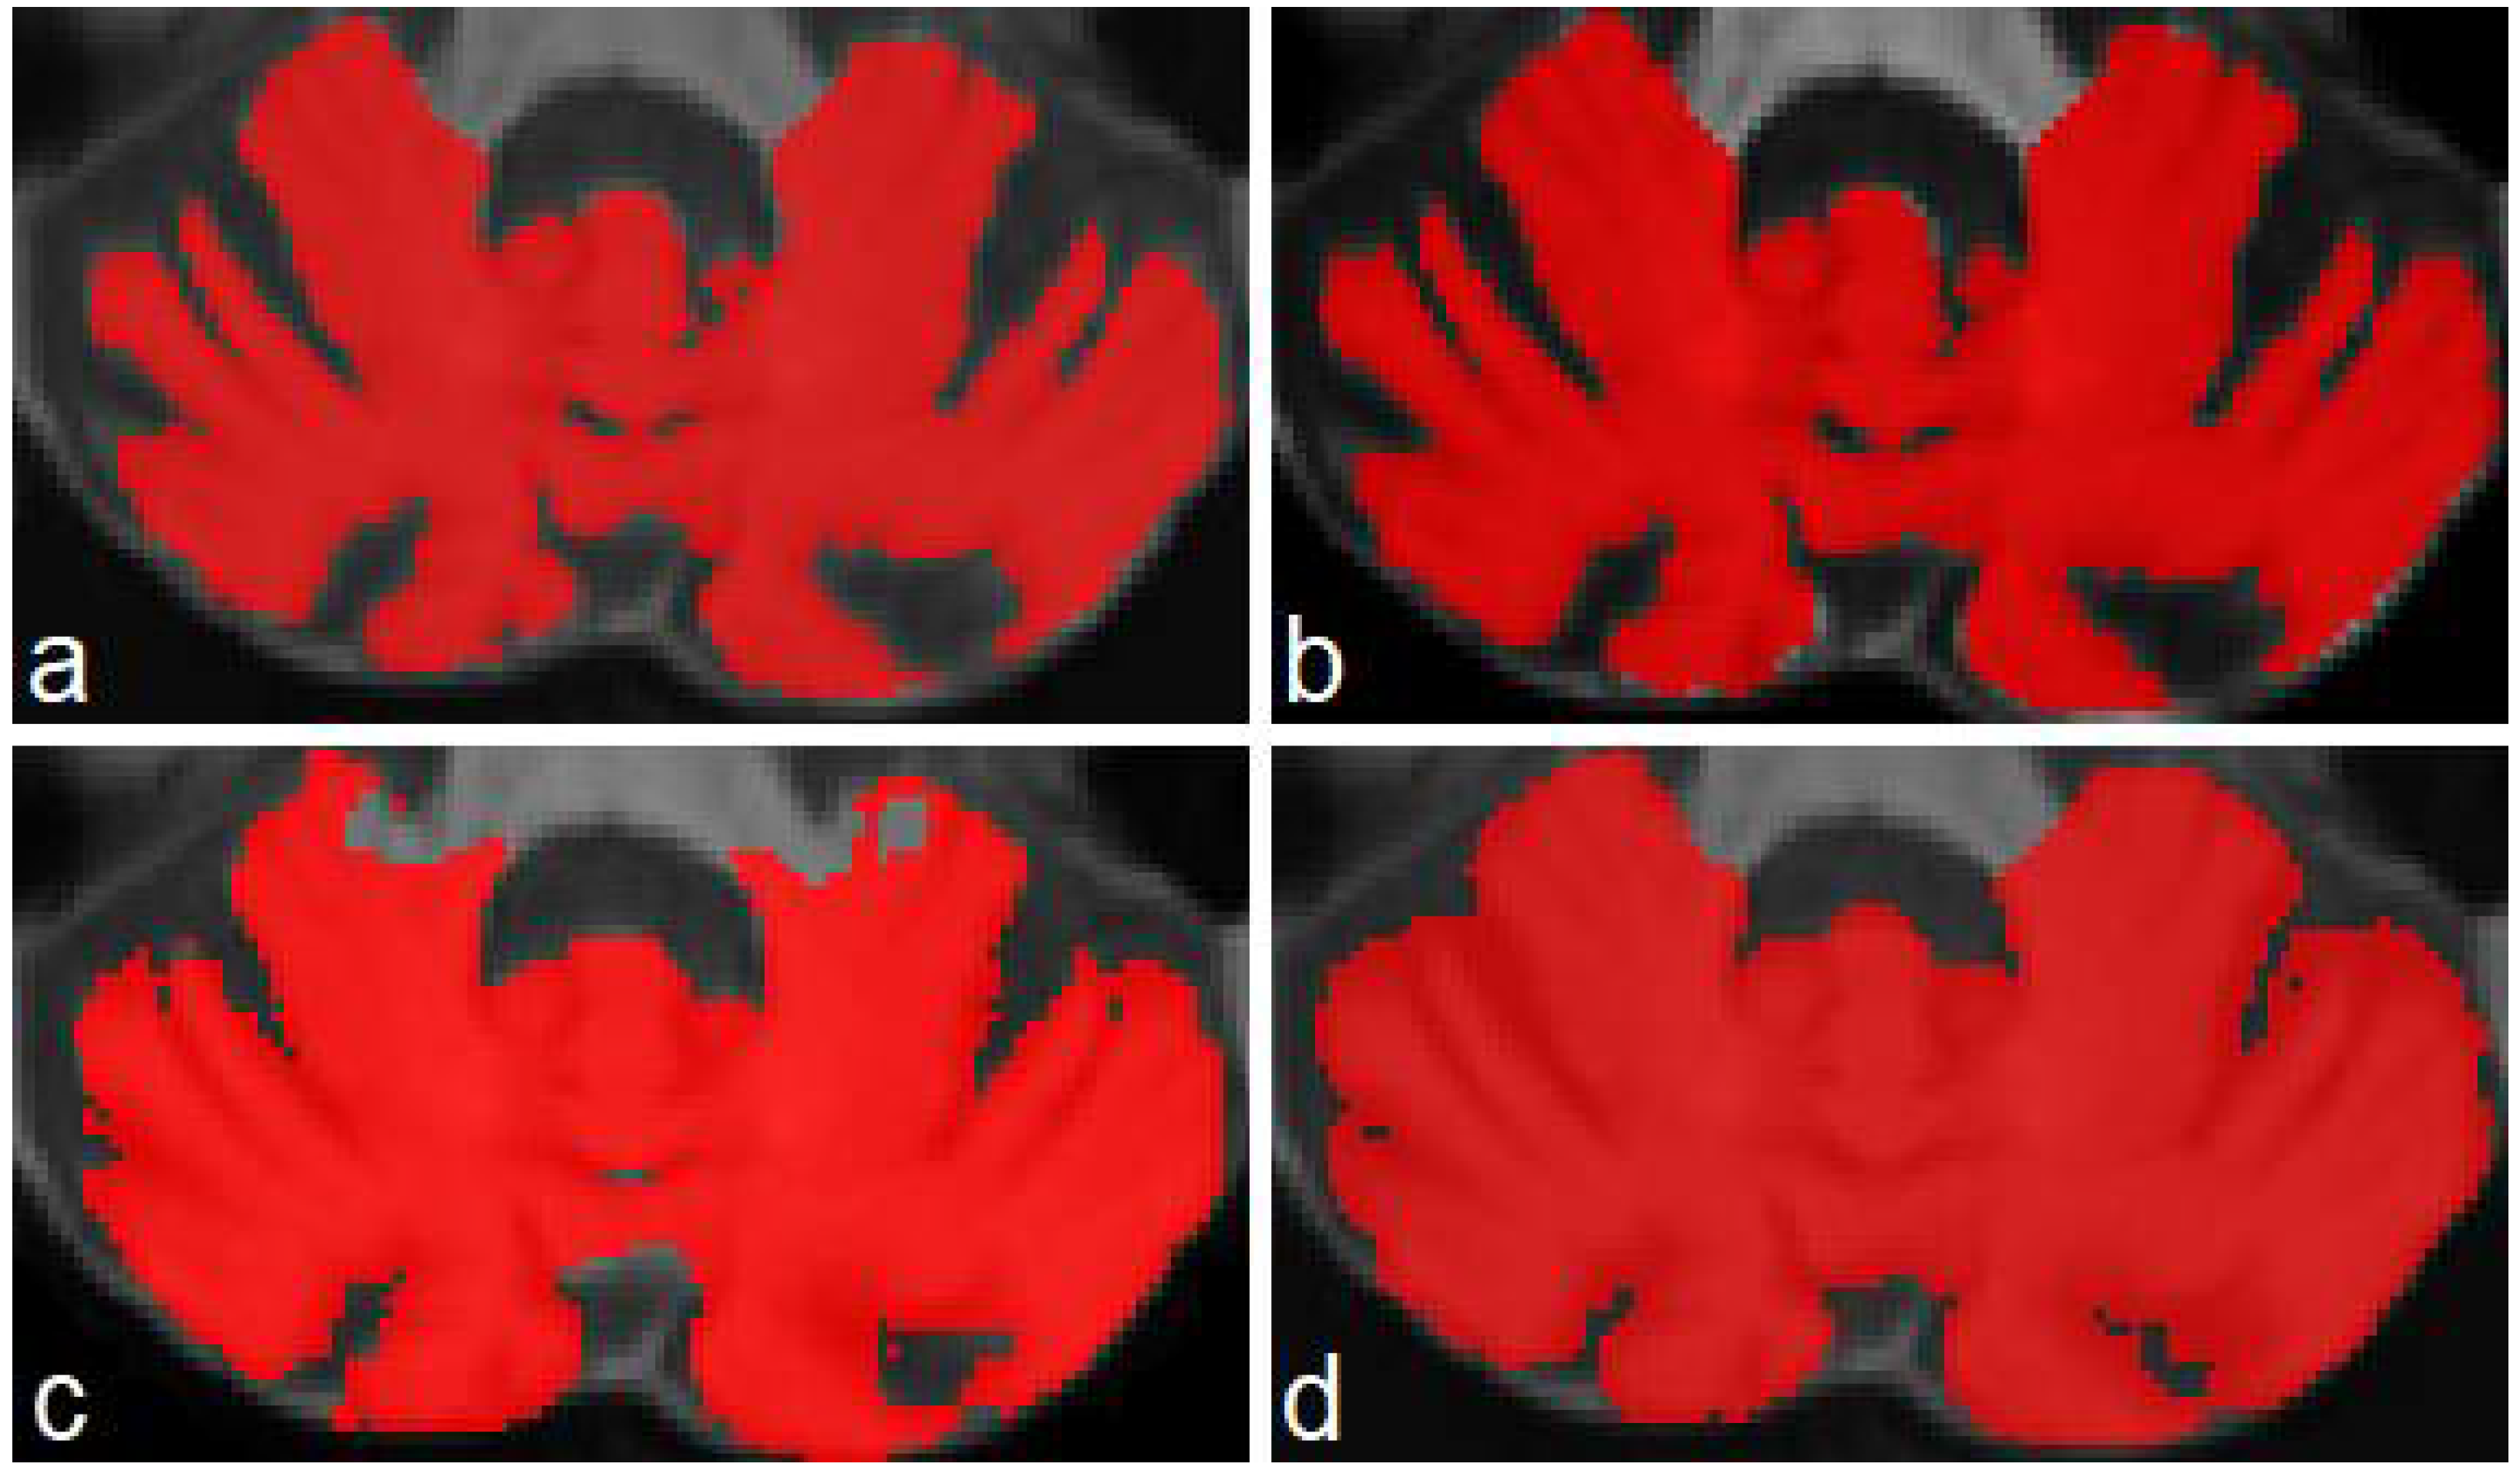

Figure 5 presents an example of segmentation produced by the three models for a subject in our dataset. As the figure shows, ACAPULCO (Figure 5d) only detected parts of the biggest fissures, while the smaller ones are classified as cerebellar tissue. CERES (Figure 5c) recognized fissures better than ACAPULCO, but some of them are also misclassified. Furthermore, some irregularities are present in the front of the cerebellum, leaving some holes in the mask produced by CERES. Segmentations obtained by model M2 (Figure 5b) are very close to the real ones, correctly recognizing most of the fissures.

Figure 5.

Example of segmentations produced by the approaches for a sample image from our dataset. Original mask (a), followed by segmentation produced by M2 (b), CERES (c) and ACAPULCO (d).

As can be seen, our model M2 achieved higher DSC than both methods. Mean DSC were 0.973, 0.903 and 0.924 for M2, Acapulco and CERES, respectively. CERES performed better than ACAPULCO in the segmentation, but in general both methods only identify the largest fissures, and a substantial part of the small fissures is misclassified. We think that this event is related with the segmentations used in both methods as a training/knowledge base, since both methods were used without any modification. The best behavior for both methods was on segmenting the first resonance image, corresponding to a healthy control.